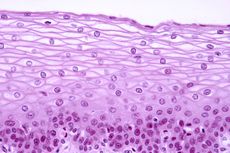

Sel-sel epitel tersusun rapat dengan tidak adanya ruang antarsel untuk membentuk penghalang atau pelindung bagi tubuh kita.

Jaringan epitel adalah salah satu jaringan dasar yang dibentuk dari kumpulan sel-sel, tersusun rapat, yang dibatasi oleh substansia interselularis